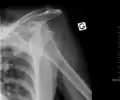

| Anterior dislocation of the left shoulder. | |

In over 95% of shoulder dislocations, the humerus is displaced anteriorly.[7] In most of those, the head of the humerus comes to rest under the coracoid process, referred to as sub-coracoid dislocation. Sub-glenoid, subclavicular, and, very rarely, intrathoracic or retroperitoneal dislocations may also occur.[8]

Anterior dislocations are usually caused by a direct blow to, or fall on, an outstretched arm. The person typically holds his/her arm externally rotated and slightly abducted.

An anterior dislocation of the shoulder An anterior dislocation of the shoulder